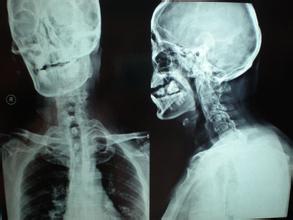

强直性脊柱炎患者普遍都伴有骨质疏松,以椎体改变比较明显,并且多伴有骨质增生、韧带骨化和骨关节硬化等,一般常常是骨质增生和骨质疏松同时并存,以脊柱各椎体表现最为明显。强直性脊柱炎晚期有少数患者马尾神经受损出现慢性进行性马尾神经综合征。